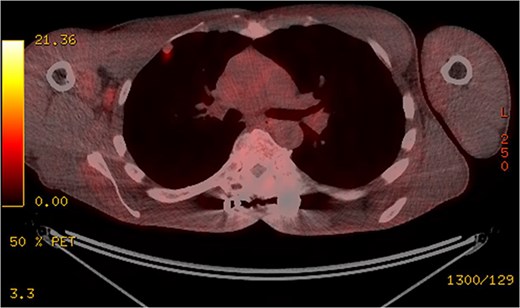

Subsequent computed tomography (CT) scan and positron emission tomography (PET) scan (Figs 2 and 3) confirmed the presence of three nodules in the right lung, suspicious for sarcoma metastases. An anterior, pleural-based upper lobe lesion, a posterior lower lobe lesion, and a lesion located at the bifurcation of his right middle and lower lobes.

Transverse and saggital views of the three nodules identified on an investigative CT scan.

The pleural-based anterior right lobe lesion showed fluorodeoxyglucose uptake on a PET scan.